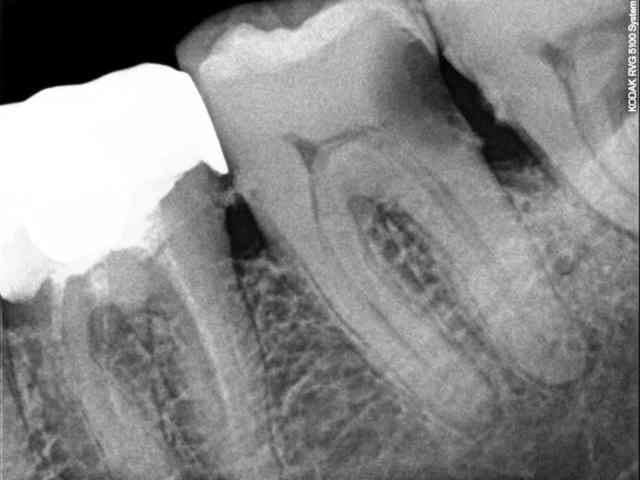

Patient fumeur, non venu depuis 2 ans, consulte pour une douleur au froid sur la 37.

Parodontite chronique/tartrique, 37 non mobile, recession gingivale de 2mm.

- alvéolyse horizontale avec sans doute déjà 2 ou 3 mm d'os perdu

- carie volumineuse et très cervicale

- probablement nécrose partielle sur la racine distale

A la rigueur tu pourrais te dire que l'avéolyse va te permettre de couronner sans avoir besoin de faire d'élongation coronaire, mais je pense que l'élément stratégique va être la furcation, l'as-tu sondée ? Si comme on peut le présumer, elle est déjà bien entamée, moi je ne garderais pas la dent.

Je suis surpris que l'extraction soit envisagée sur ce genre de dent cariée...... Sur la radio (pas de pano donc pas d'autres élements) je ne vois pas de parodontite chronique....) > la perte osseuse est à mon sens liée à la carie proximale avec probablement un tassement alimentaire. Une gingivite est probable par ailleurs.

Sur la radio effectivement pas de grosse atteinte paro visible. Mais en bouche, les incisives mdr ont légère mobilité, les furcations des molaires mxr presques visibles à l'oeil nu. L'alvéolyse n'est pas du qu'à la carie.